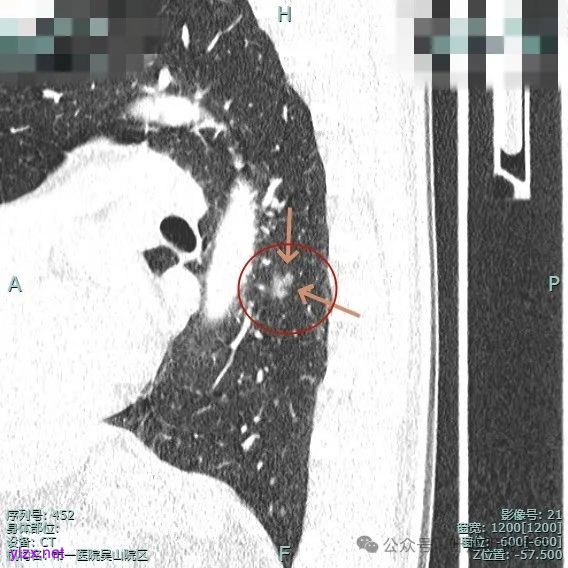

表面有浅分叶征,整体轮廓清。

灶内小空泡征,边缘略显毛糙,整体轮廓较清。

主病灶血管进入,灶内空泡,表面浅分叶,整体轮廓较清。